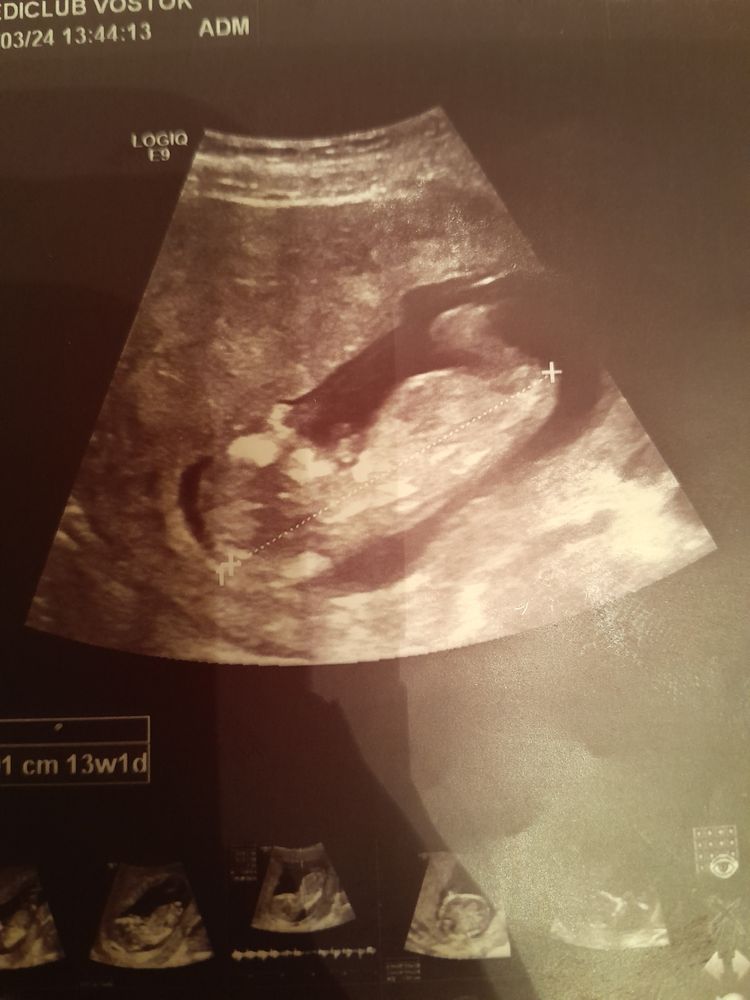

Анастасия в Благополучная беременность 2 года Мальчик или девочка фото узи Пол малыша Здравствуйте, кто разбирается видно ли кто мальчик или девочка по половом бугорку? Посмотрите еще 20 записей на эту тему Отменить Ответить Таня Мне кажется скорее девочка, чем мальчик. Ну по крайней мере ничего не торчит) 05.04.2024 Ответить Family А где фото ? 04.04.2024 Ответить Анастасия Family, не прикрепилось почему то сразу, прикрепилиа уже 04.04.2024 Ответить Кровь на определение пола ребенка НИПТ и новости) Чаты Беременных Выберите чат: Январята-2026 Февралята-2026 Мартята-2026 Апрелята-2026 Майчата-2026 Июнята-2026 Июлята-2026 Августята-2026